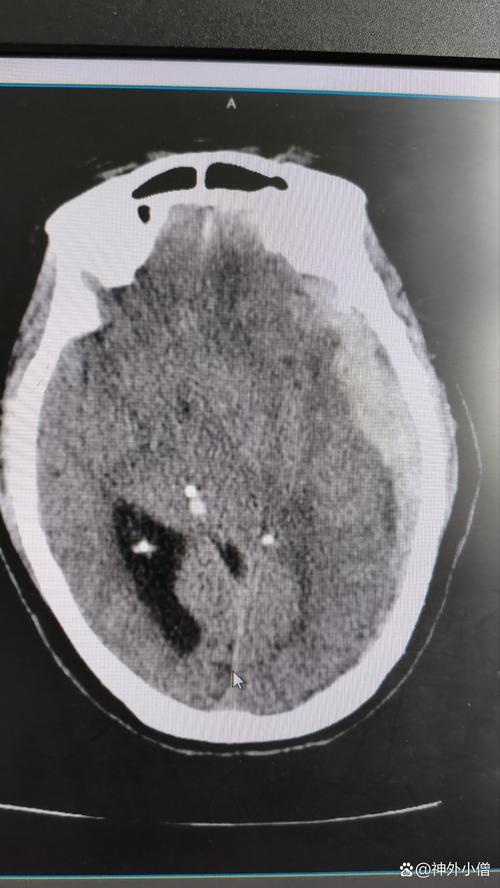

- 诊断: 一旦怀疑脑梗,医生会立即安排头部CT扫描(早期可能显示不清,但可排除出血)和磁共振成像,特别是DWI序列,能非常早期、准确地发现梗塞灶,CTA(CT血管造影)或MRA(磁共振血管造影)可以帮助评估血管有无狭窄或闭塞。